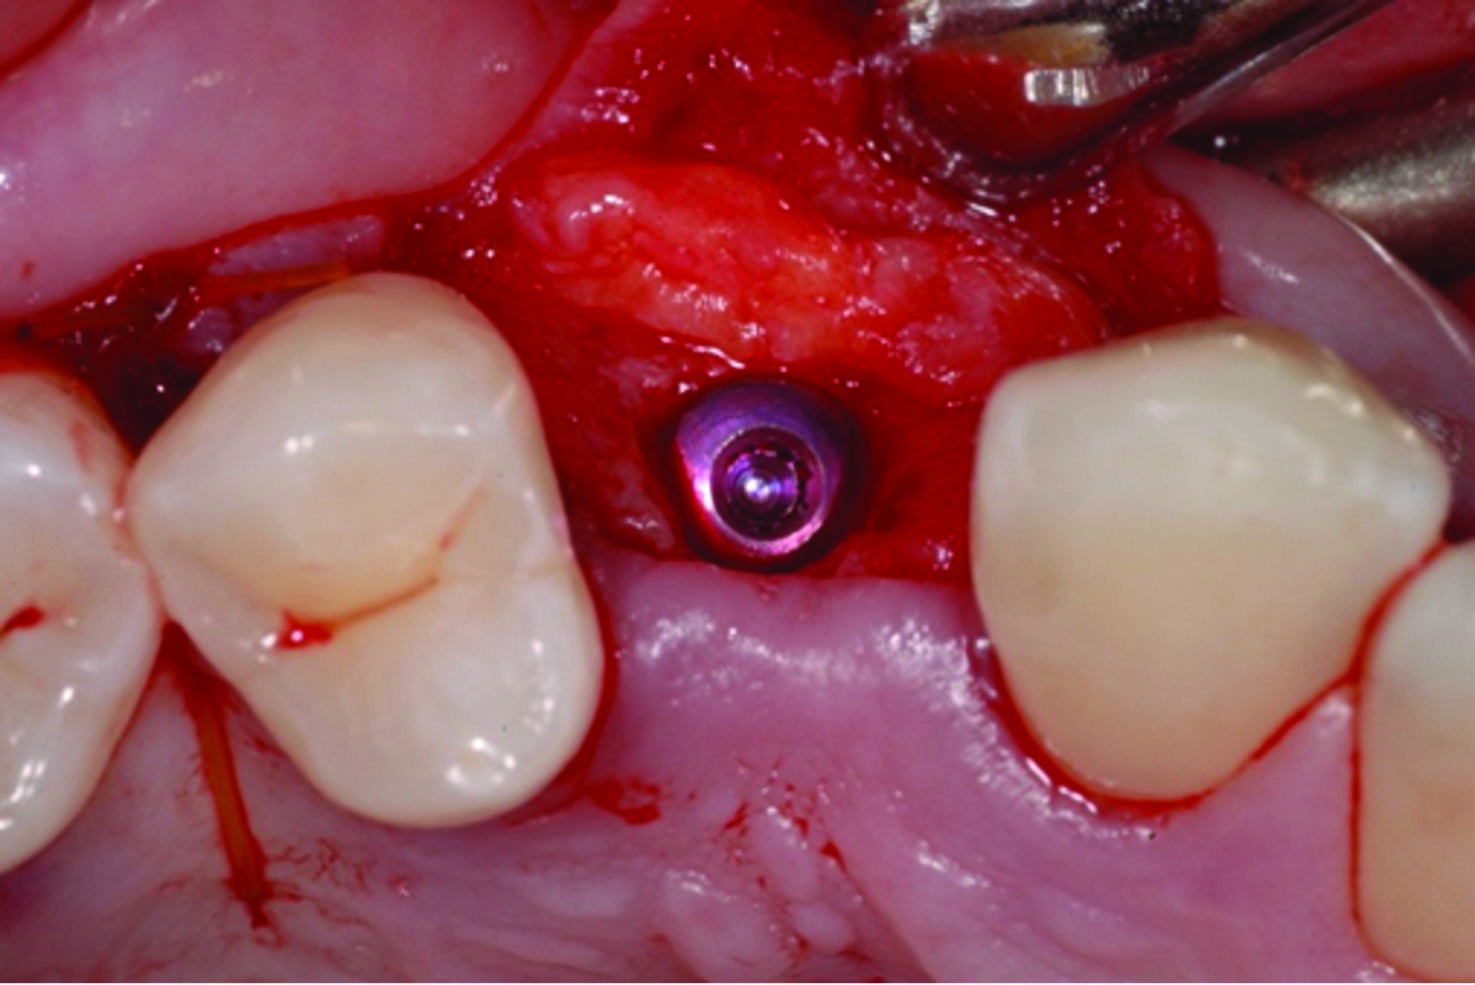

Fig 6 through Fig 8. Example of increasing KMW with an APF at implant uncovery. Fig 6: initial presentation showing lack of KMW; Fig 7: healing abutment placement with APF; Fig 8: 2 months post-treatment. (The dotted lines indicate the MGJ.) Fig 9 through Fig 11. Example of increasing KMW with an APF and FGG at implant uncovery.

Figure 6

Figure 7

When a lack of KMW is noted, suggested treatments may include the use of an apically positioned flap (APF)20 (Figure 6 through Figure 8) or a combination of APF with an FGG (Figure 9 through Figure 11) or tissue alternatives.21 Because of the nature of the recipient site preparation for an FGG or tissue alternative, such as ADM, AXDM, or CM, there is a risk of wound dehiscence and a potential negative effect on the healing of the bone augmentation or on osseointegration if the grafting is done at the time of ridge augmentation or implant placement. Therefore, the preferred treatment time for increasing KMW with an FGG, ADM, AXDM, or CM is either prior to implant placement or after healing of the implant at the healing abutment connection (Table 1). MT can be increased using the roll technique (Figure 12 through Figure 14)22,23 or by adding a CTG (Figure 15 and Figure 16), ADM, AXDM, or CM (Figure 17 and Figure 18), either at the time of implant placement or healing abutment connection (Table 1).24,25